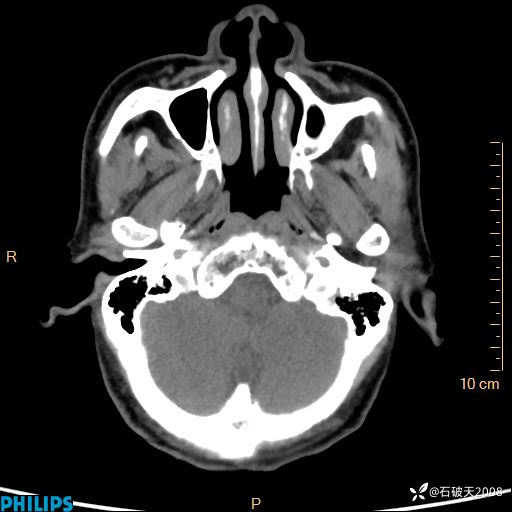

平扫